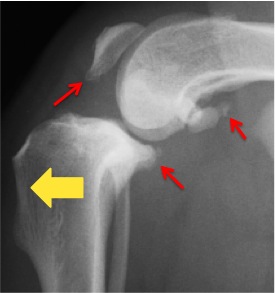

イメージとしては三角形の積み木を上から押すと前に出るのと同じです。 この力に前十字靭帯が耐えきれなくなると断裂してしまうのです。 断裂してしまったら手術をしてあげないと改善しない子が多いです。 断裂してしまった子は下のレントゲンのように脛骨が前方に変位し、関節炎が進み骨が滑らかでなくなってしまいます。

*